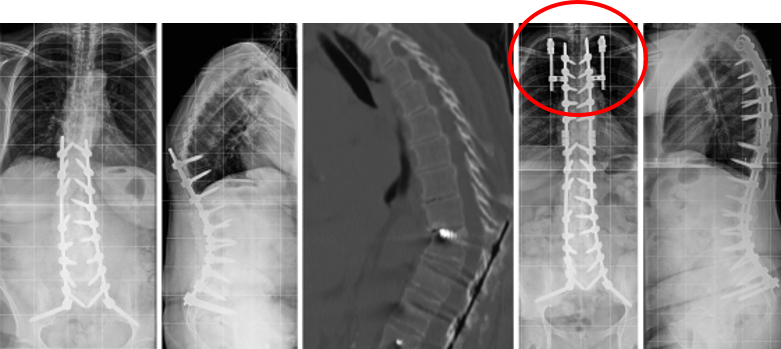

图12 CBT+TT+多棒固定

CBT+TT+多棒固定

从融合节段向活动节段未行过渡性手术,导致局部应力分布不均,局部应力过于集中,也是交界性问题的危险因素之一。

长节段固定时,融合区和活动区应适当行过渡性手术,可降低PJK发生的风险。

图13 长节段全椎弓根螺钉固定,局部应力过于集中